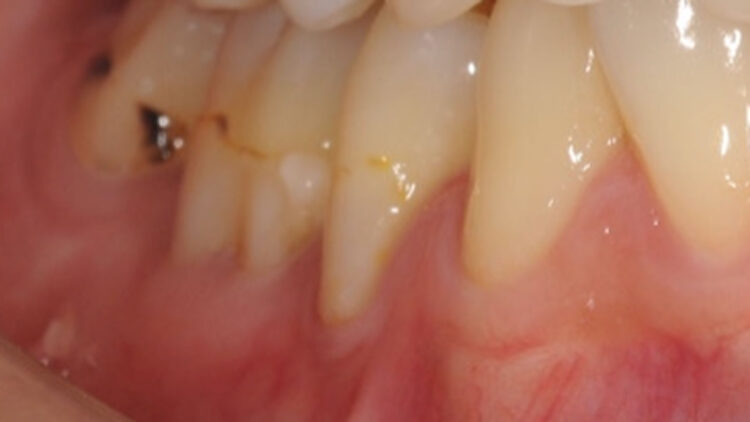

- 【術前】奥歯の歯肉退縮症例②